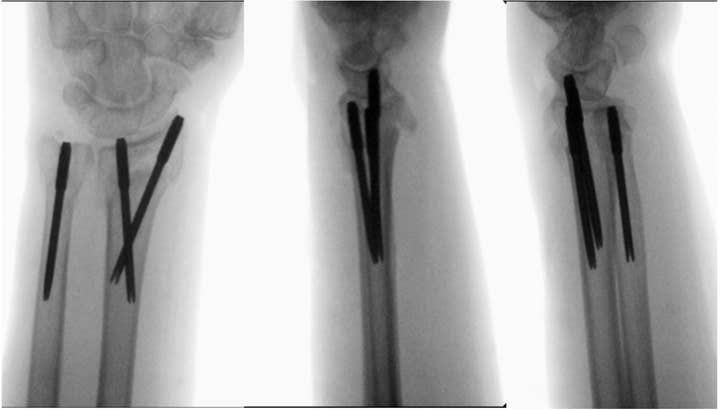

Anteroposterior, lateral, and oblique postoperative images (B) of distal radius and ulna fractures fixed with T-Pins.